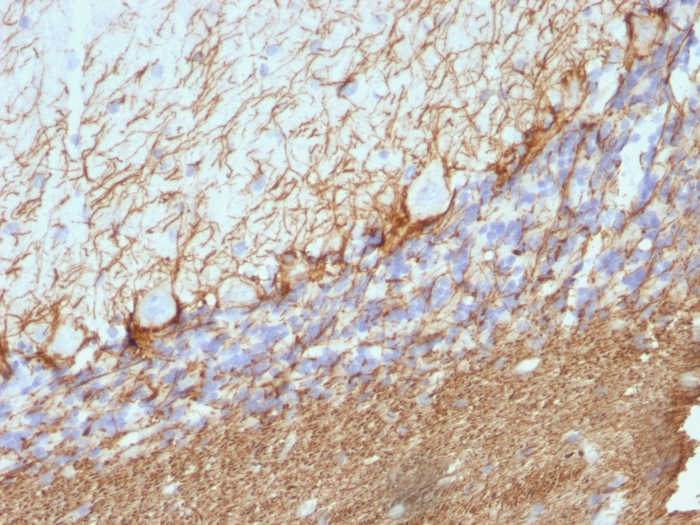

Formalin-fixed, paraffin-embedded human Cerebellum stained with Neurofilament Mouse Monoclonal Antibody (NE14).

This MAb reacts with a 200kDa protein, identified as heavy sub-unit of neurofilaments (NF-H). It reacts specifically with the phosphorylated KSP/KEP segment at the C-terminus of the heavy subunit (NF-H) of neurofilaments. After dephosphorylation of neurofilaments with alkaline phosphatase, this Ab no longer binds. Neurofilaments make up the main structural elements of axons and dendrites and are found in neurons, peripheral nerves, and sympathetic ganglion cells. Neurofilaments consist of three major subunits with molecular weights of 68kDa (NF-L), 160kDa (NF-M) and 200kDa (NF-H). Anti-neurofilament stains a number of neural, neuroendocrine, and endocrine tumors. Neuromas, ganglioneuromas, gangliogliomas, ganglioneuroblastomas, and neuroblastomas stain positively for anti-neurofilament. Neurofilaments are also present in paragangliomas as well as adrenal and extra-adrenal pheochromocytomas. Carcinoids, neuroendocrine carcinomas of the skin, and oat cell carcinomas of the lung also express neurofilament.